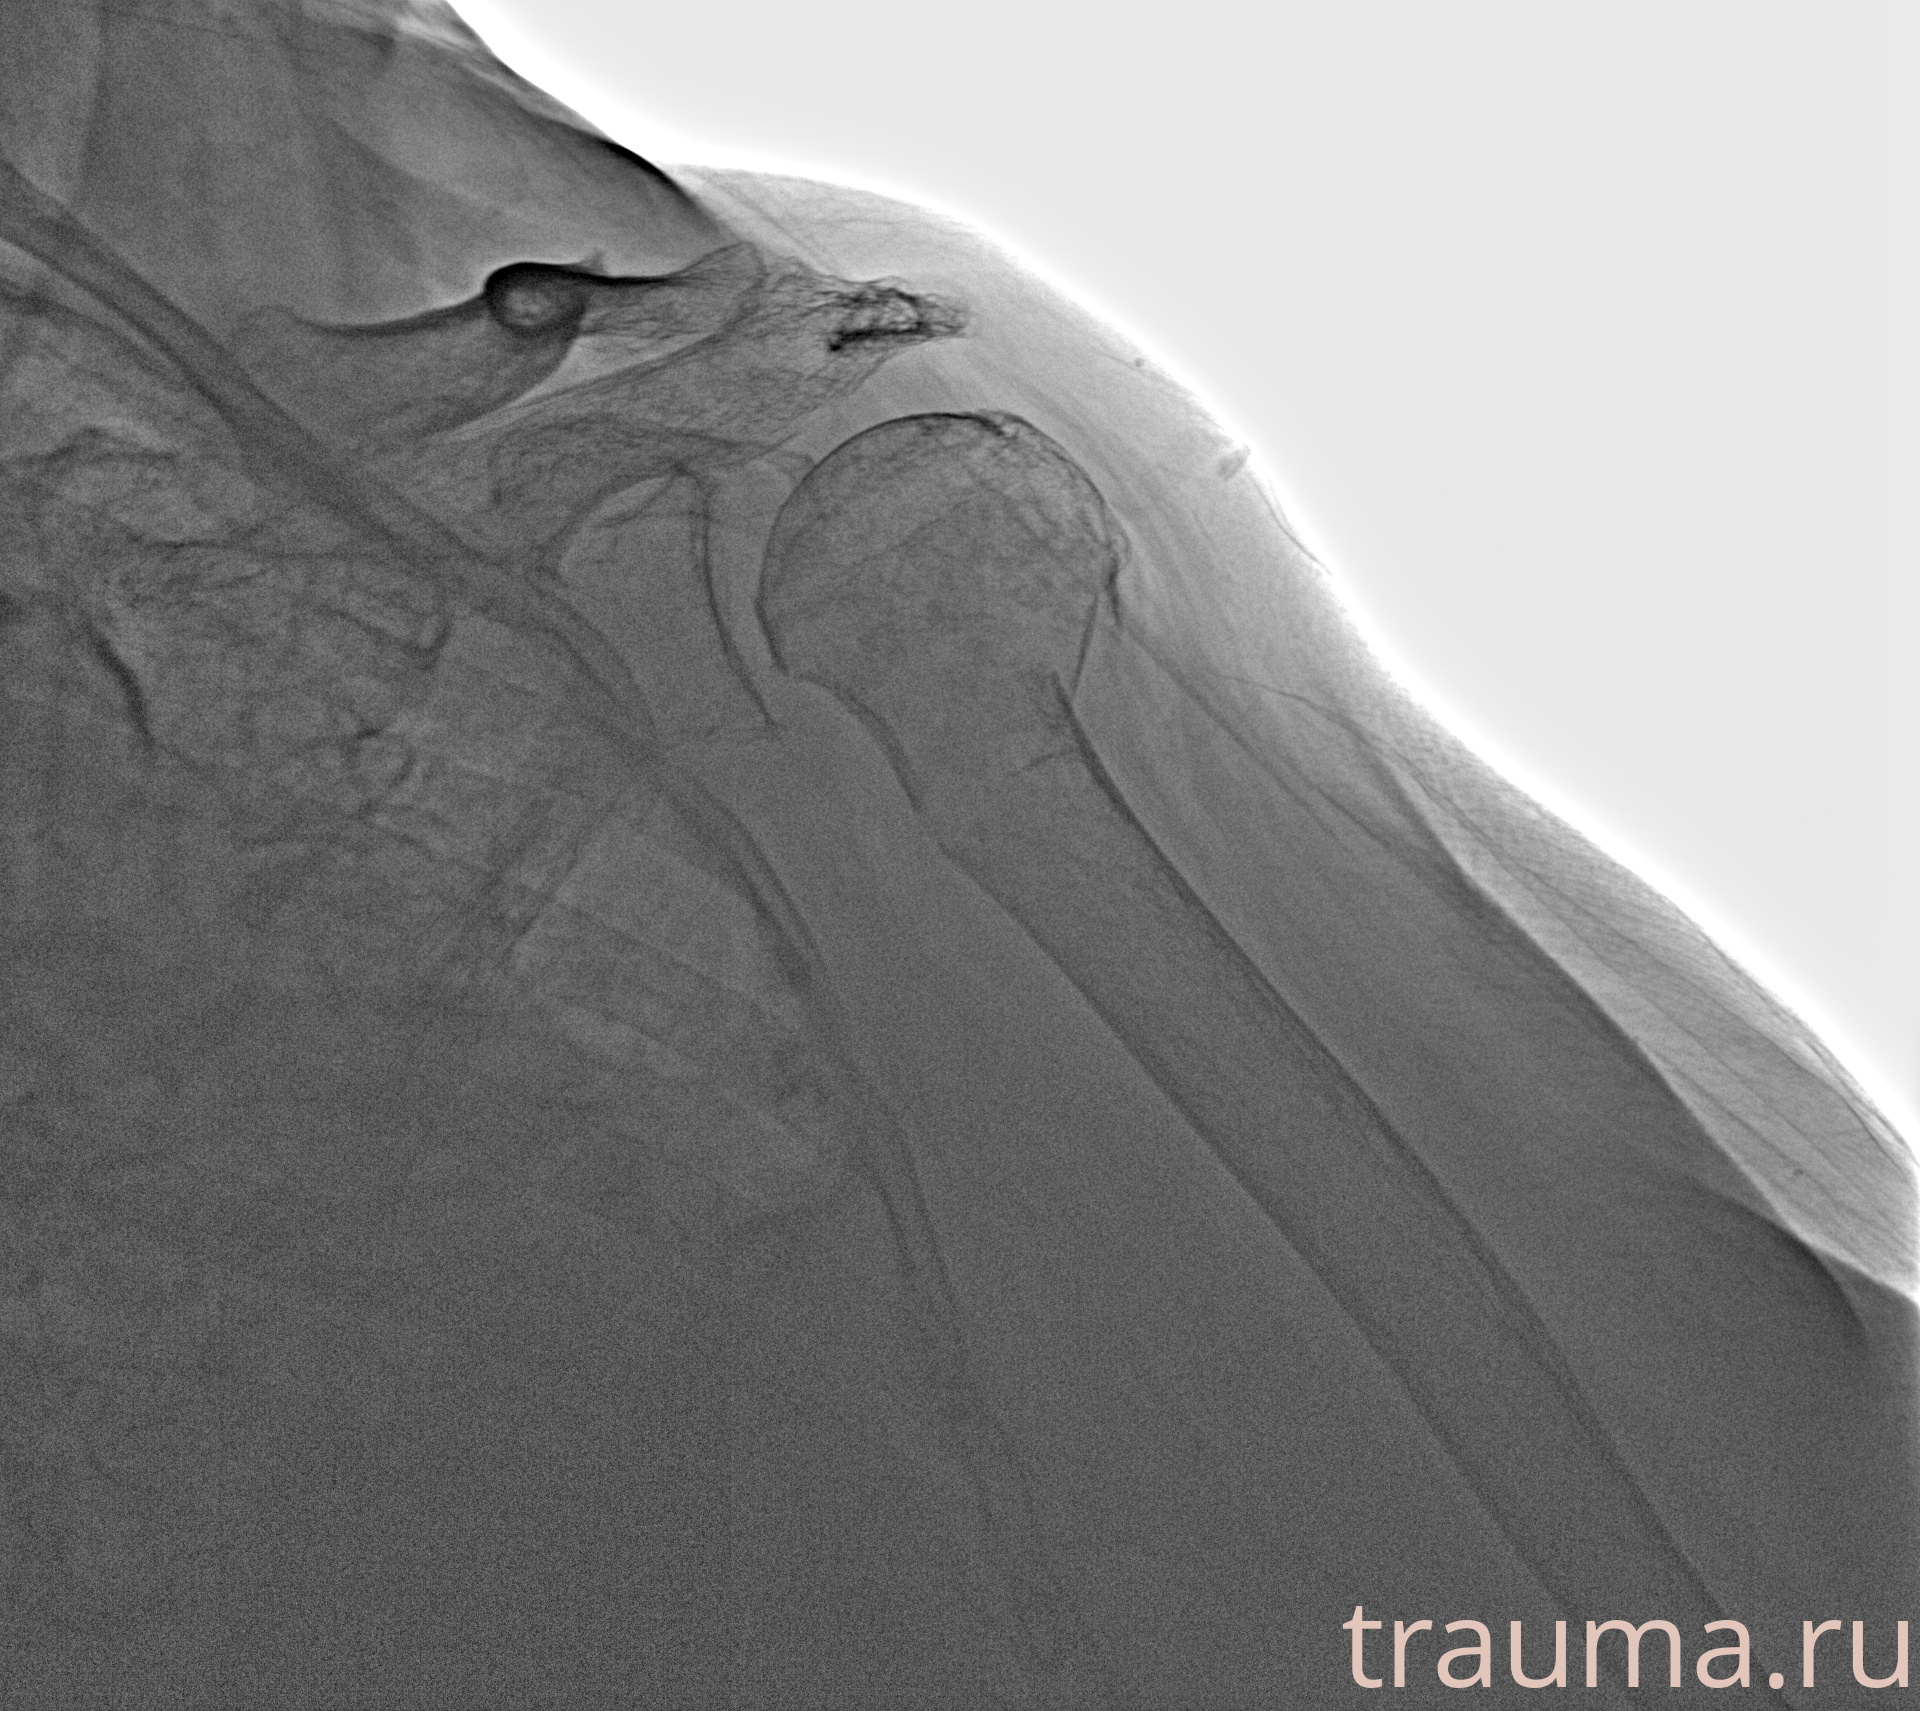

Рентгенограммы

Рентген на дому: по вашему адресу приезжает врач-рентгенолог, травматолог-ортопед с мобильным рентгеновским аппаратом, проводит диагностику травмы или заболевания, делает необходимые рентгенограммы, дает рекомендации по дальнейшему лечению. Получить качественные снимки в домашних условиях возможно благодаря уникальной методике, разработанной МосРентген Центром для института  Склифосовского